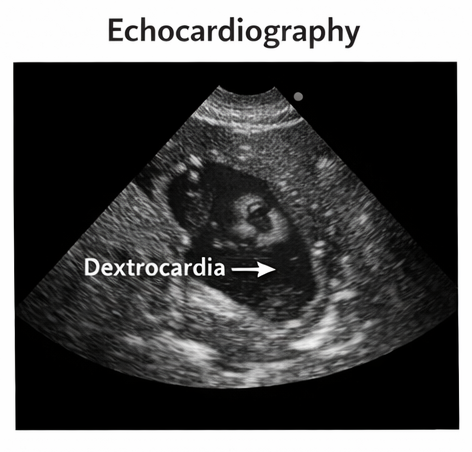

Echocardiography

Echocardiographic evaluation confirmed dextrocardia with structurally normal cardiac chambers and valves, with no evidence of congenital heart disease.

Based on clinical examination and imaging findings, a diagnosis of situs inversus totalis with dextrocardia was established.